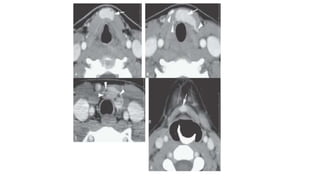

• #25 Contrast-enhanced computed tomography study of a patient with an infrahyoid ectopia of the thyroid gland shown by the arrows in all images. In (B), there is thyroid tissue not attached to the main ectopic glandular tissue, demonstrating the potential for all migrational abnormalities of the thyroid gland to result in disconnected lateral ectopic tissue (arrowheads). In (C), there are multiple small cysts within the ectopic tissue, suggesting that such ectopic tissue can develop abnormalities that might occur in normally positioned thyroid tissue (arrowheads).